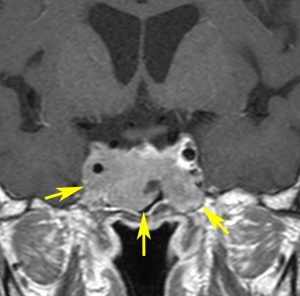

とても小さな腫瘍(微小腺腫) microadenoma

1cm以下の小さなものを微小腺腫といいます。ホルモンを異常に分泌する腫瘍は摘出する必要がありますが,そうでないものは治療の必要がありません。微小腺腫を数年観察しても増大する確率は10%くらいです。逆に,それ以上に大きなものだと,50%くらいの確率で増大します。

日本で汎用されているものでは最も解像力が高い3テスラMRIで撮影された,ガドリニウム増強像です。左側の画像では下垂体の大きさと形は正常に見えます。画像を調整すると,下垂体の内部,右端(黄色の矢印の先)に6mmくらいの小さな腺腫がみつかりました。MRIの性能がよくなったことによって数mmの小さなものも診断できるようになりました。